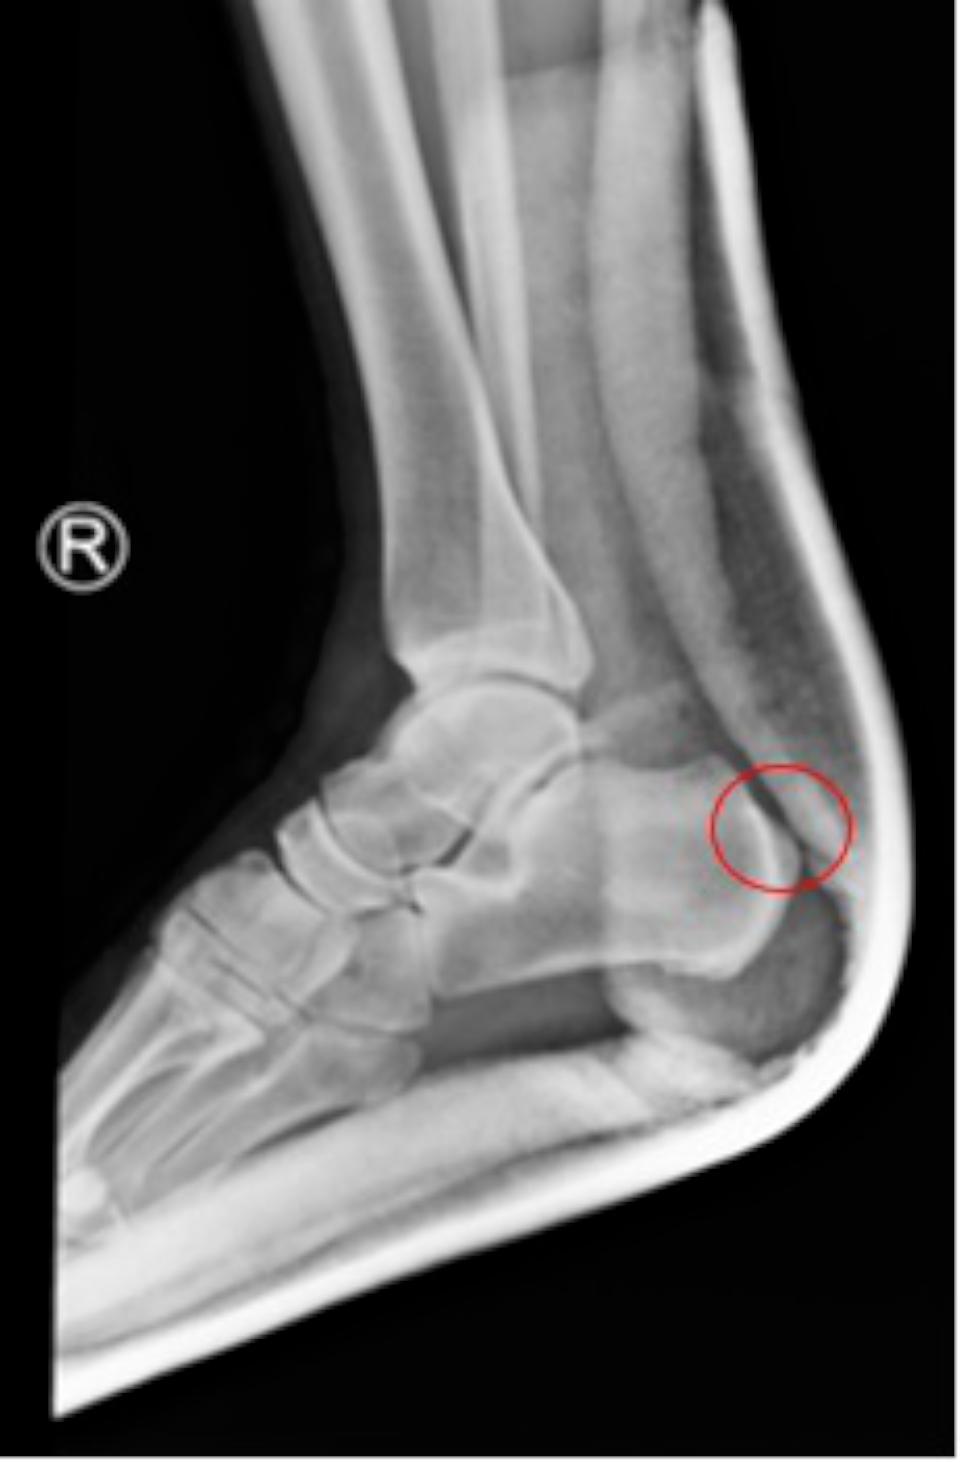

高市劉姓員警退休後陪伴高齡母親,種植竹筍過程突感足底疼痛,就醫治療兩年未見改善,經友人轉介七賢脊椎外科醫院骨關節科主任吳宗哲確診足跟骨骨刺,肇因阿基里斯肌腱過度拉扯,術後恢復正常生活。

吳宗哲說,跟骨骨刺可能出現疼痛、灼熱、腫脹等症狀,久站、運動傷害、肥胖、扁平足、高足弓等是好發族群,提醒足跟疼痛持續逾一週,建議就醫檢查治療。圖/七賢脊椎骨科醫院提供、文/高培德